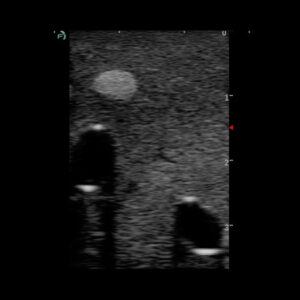

Le fantôme de biopsie mammaire présente une forme adaptée à l’entraînement aux procédures de biopsie du sein.

Les 11 masses complexes positionnées de manière aléatoire s’apparentent à des nodules et micro-nodules de diverses natures.

Modèle de fantôme standard pour la pratique des fondamentaux de la biopsie.